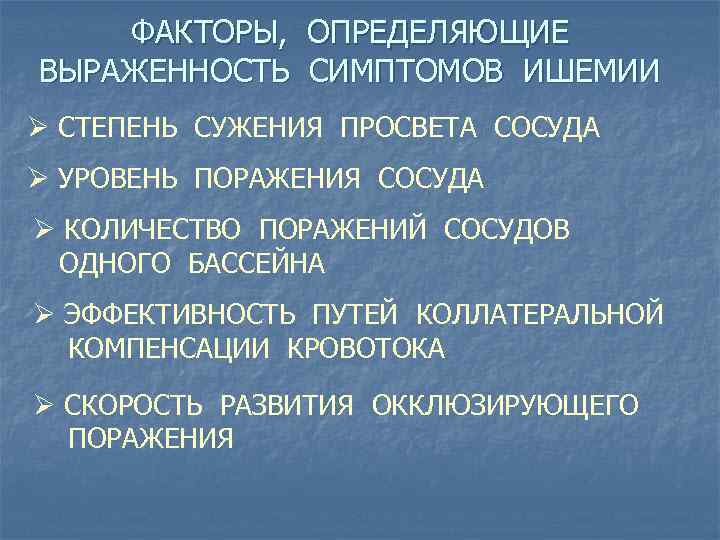

ФАКТОРЫ, ОПРЕДЕЛЯЮЩИЕ ВЫРАЖЕННОСТЬ СИМПТОМОВ ИШЕМИИ Ø СТЕПЕНЬ СУЖЕНИЯ ПРОСВЕТА СОСУДА Ø УРОВЕНЬ ПОРАЖЕНИЯ СОСУДА Ø КОЛИЧЕСТВО ПОРАЖЕНИЙ СОСУДОВ ОДНОГО БАССЕЙНА Ø ЭФФЕКТИВНОСТЬ ПУТЕЙ КОЛЛАТЕРАЛЬНОЙ КОМПЕНСАЦИИ КРОВОТОКА Ø СКОРОСТЬ РАЗВИТИЯ ОККЛЮЗИРУЮЩЕГО ПОРАЖЕНИЯ